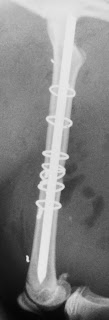

Συντριπτικό κάταγμα διάφυσης μηριαίου οστού γάτας: οστεοσύνθεση με ήλο και σύρματα.

Πλάγια ακτινογραφία μετά από οστεοσύνθεση με ήλο και σύρματα